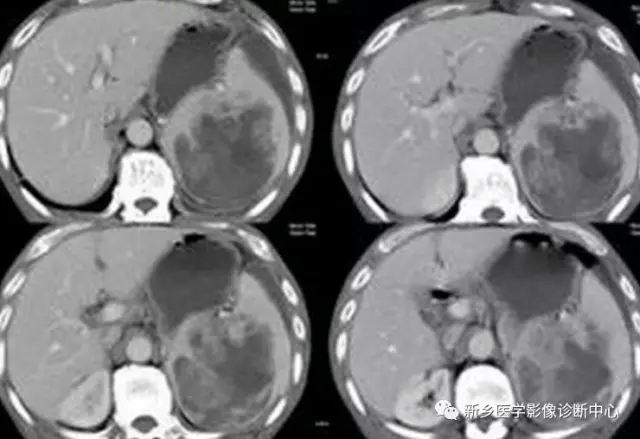

5 肝破裂出血

文章图片